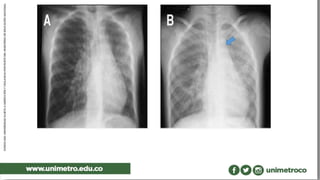

Ecografía de tórax fetal en situs inverso.

la punta delcorazón se encuentra en el LD Hígado en el LI Estómago en el LD Ciego en el LI. imagen en espejo CAUSAS enfermedad genética autosómica recesiva TIPOS dextrocardia levocardia DIAGNÓSTICO radiografía TC Imagen de resonancia magnética Ultrasonografía ECOGRAFIA TRATAMIENTO Es sintomático Asociada a sx kartagener e ivermark

Ecografía de tóraxfetal en situs inverso.